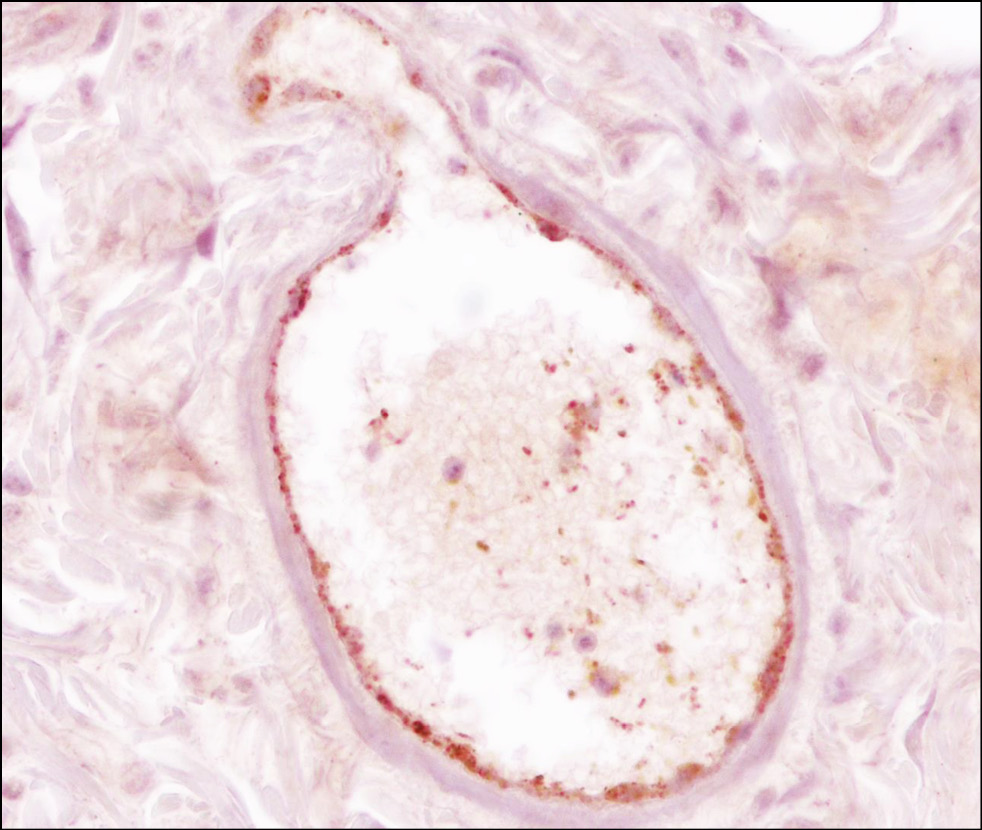

При исследовании препаратов интактной кожи было выявлено всего 3 кровеносных сосуда в составе гиподермиса: 2 крупных (Sср = 604,16 ± 0,61 мкм2) и 1 очень крупный (Sср = 2578 мкм2; рис. 1).

Рис. 1. Интактная кожа бедра крысы — крупный сосуд в составе дермы; иммуногистохимическое окрашивание с антителами к фактору фон Виллебранда; объектив ×40, окуляр ×10.

Fig. 1. Intact skin of the rat thigh. A large blood vessel in the dermis. Immunohistochemical staining with anti–von Willebrand factor antibodies; objective ×40, eyepiece ×10.